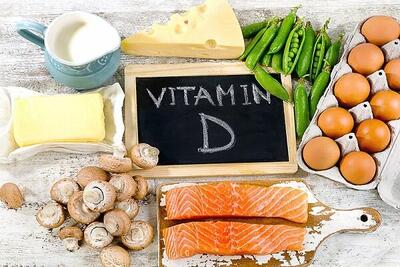

کاهش وزن از نشانههای کمبود این ویتامین است

در این این مطلب به علائم کمبود ویتامین B در بدن اشاره شده است.

کمبود این ویتامین سبب ریزش وزن بدن می شود و افسردگی و اختلالات در اندام های مختلف را به همراه دارد.

کمبود این ویتامین در بدن با علائمی همچون ریزش مو، افسردگی و افزایش وزن همراه است

کمبود این ویتامین در بدن با علائمی همچون ریزش مو، افسردگی و افزایش وزن همراه است و تأثیرات مخرب آن بر سلامت بدن بیشمارند.

اندیشه معاصر- آنچه که از مصرف ویتامین D نمی دانید اندیشه معاصر

یک عضو هیئت علمی دانشگاه علوم پزشکی اصفهان، گفت: افرادی که دچار چاقی و اضافه وزن هستند بیشتر در معرض کمبود ویتامین D قرار دارند. همچنین، کم تحرکی میتواند مانع جذب ویتامین D در بدن شود.